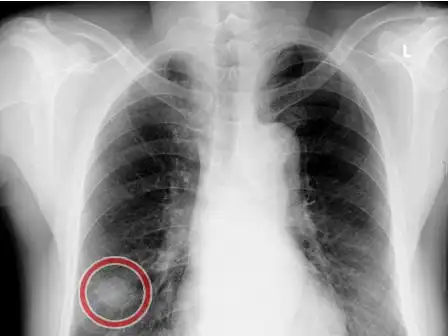

早期肺癌ct图

基础学习中央型肺癌典型征象